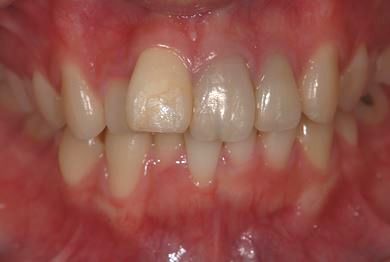

セラミック治療

| 性別/年齢 | 女性 / 20歳 | ||||||||||||||||||||||||||||||||

| 主訴 | 神経が死んで来ている歯が痛むので、治療をして欲しい。歯並びも良くできるのであればして欲しい。 | ||||||||||||||||||||||||||||||||

| 治療方針 | ジルコニアオールセラミック(クラウン1本、ブリッジ3本)、セラミック用土台2本 | ||||||||||||||||||||||||||||||||